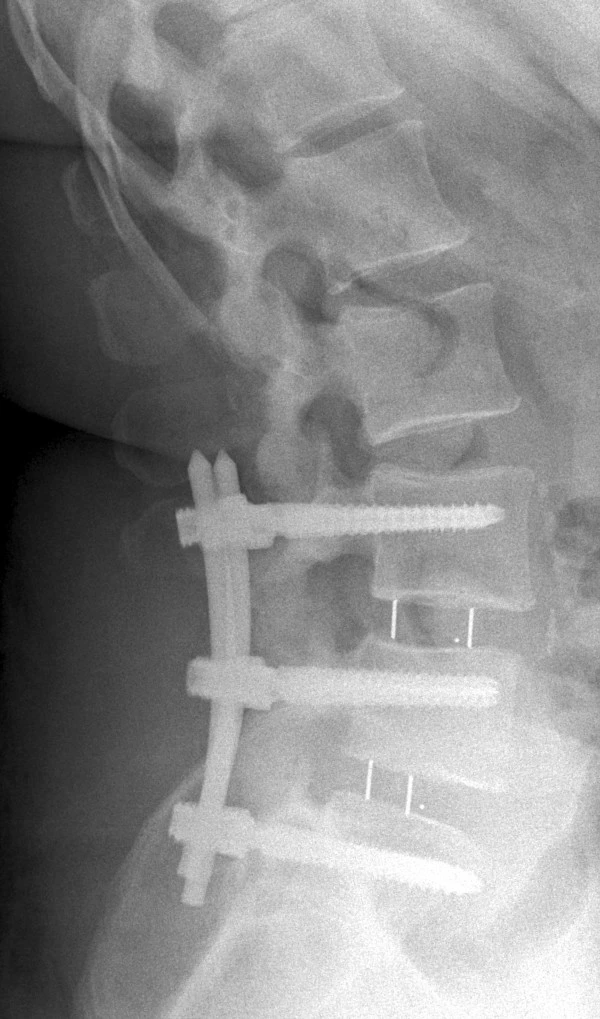

An X-ray of a spine with an interbody fusion device (IFD) inserted. Kate was working with a device that allows researchers to test IFDs without having to put them into human spines first. Picture licensed under Creative Commons, CC BY 4.0. (From Leute et al. 2015. J Med Case Reports 9, 22. https://doi.org/10.1186/1752-1947-9-22 )

Kate worked over the summer on determining the appropriate spinal stiffness setting in their desktop device that will allow the testing of Interbody Fusion Devices (IFDs) used in spinal surgery.

Kate did her internship in the Computational Mechanics and Materials Lab (CMML) of Dr. Matthew W. Priddy at MSU. She was part of a team that has developed a desktop device for testing new spinal implant equipment. The machine serves as a substitute for the human cadavers that are otherwise required for such testing.